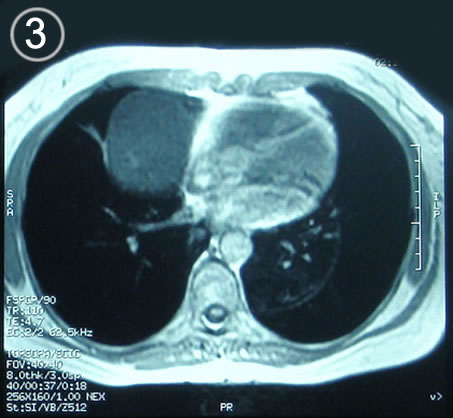

Resonancia Corte axial 4 supra diafragnatico

Corte Axial en secuencia T1

Corte mediastinico paracardiaco.

Inmediatamente por debajo o distal a la lesión, imagen cardiaca luce un pericardio de aspecto normal.

la lesión redondeada ya no es visible.